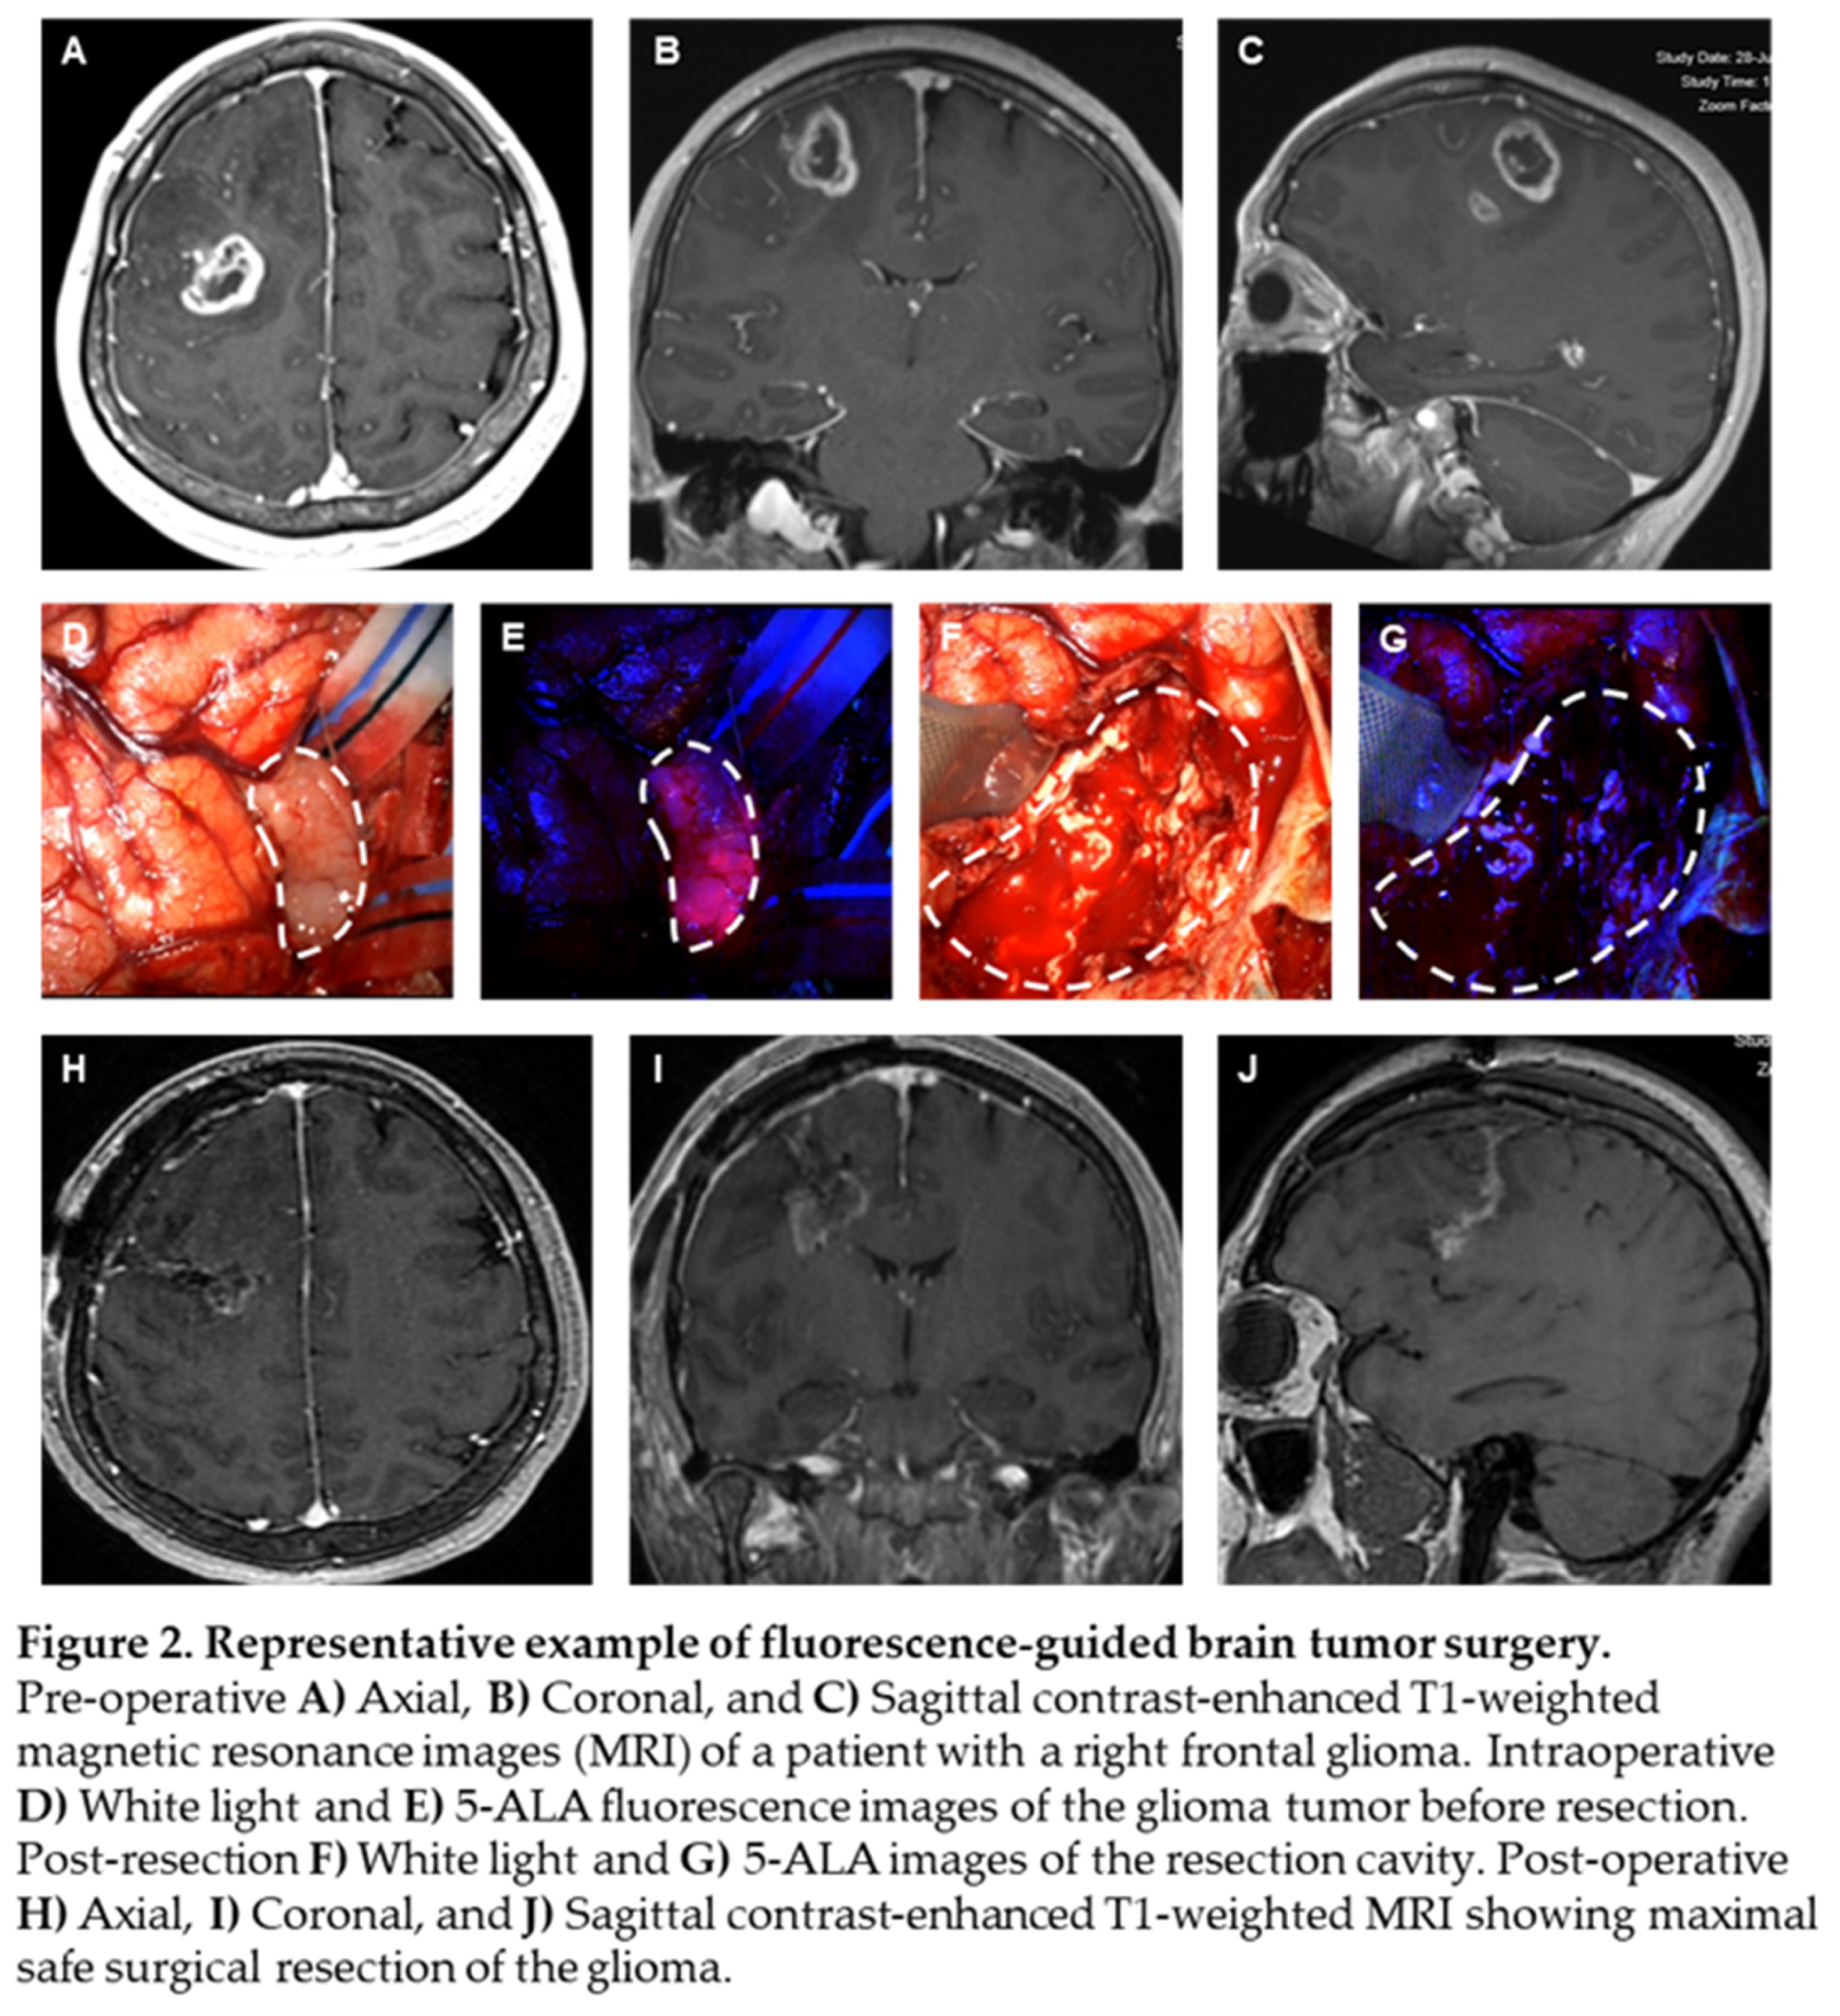

5-ALA, given intravenously at 20 mg/kg 3 hours prior to induction of anesthesia, can effectively identify high grade glioma tissue during surgery. We present a case of a patient with a right frontal, ring-enhancing intra-axial brain lesion, as visualized on axial, coronal, and sagittal MRI scans, respectively (Figure 2A-C). Intraoperative white light microscopy shows flesh colored tumor tissue (Figure 2D, white dashed border), which emits 5-ALA fluorescence (Figure 2E, white dashed border), allowing for the neurosurgeon to achieve maximal extent of resection of tumor tissue without sacrificing neighboring brain tissue. Blood from surrounding tumor vasculature at the time of surgery can obscure the surgeon’s ability to differentiate infiltrative tumor (Figure 2F, white dashed border). Persistence of 5-ALA signal allows for the surgeon to continue resection within a margin of safety (Figure 2G, white dashed border). Post-operative MRI scans demonstrate maximal extent of resection, with effective removal of the bulk of the ring-enhancing tumor (Figure 2H-J) from the patient’s brain and the absence of neurological deficits.